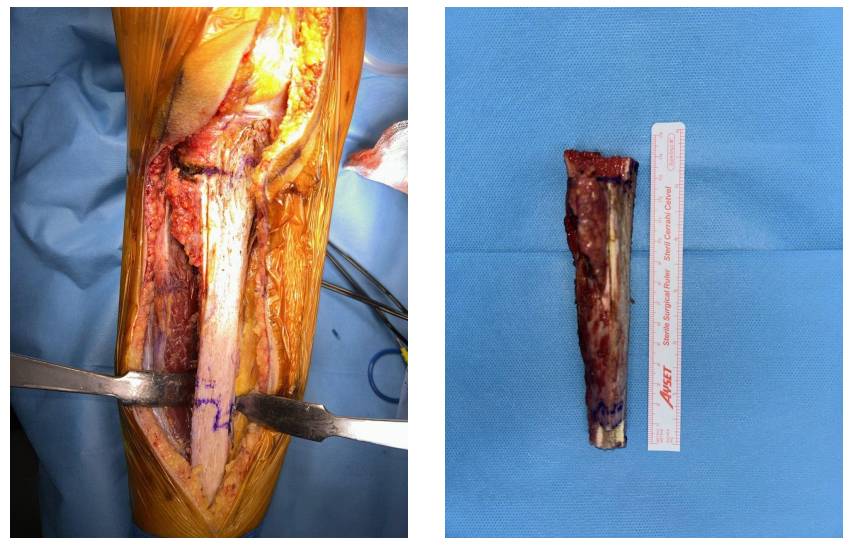

Ameliyat Esnası: Tibia mediali ortaya konduktan sonra proksimalden düz distalden basamak osteotomisi yapılarak kitlenin çıkarılması görülmekte